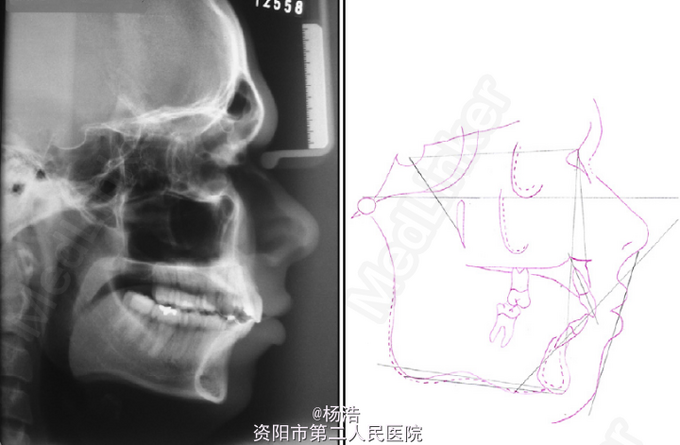

主诉:唇突,上前牙间隙 男,21岁,凸面型,面下1/3短,唇前突伴下唇前突,颏肌紧张,TMJ正常,上颌中切牙间5mm间隙,下中线右偏1mm,唇休息位和闭合位上中切牙都因前突而暴露。覆盖14mm,深覆合 根尖片示上下颌四个6都因龋坏拔除 侧位片:短面型,低角,严重骨性II类,ANB:9°

凸面型,面下1/3短,唇前突伴下唇前突,颏肌紧张,TMJ正常,上颌中切牙间5mm间隙,下中线右偏1mm,唇休息位和闭合位上中切牙都因前突而暴露。覆盖14mm,深覆合 根尖片示上下颌四个6都因龋坏拔除 侧位片:短面型,低角,严重骨性II类,ANB:9°

诊断:骨性II类,上颌前突,牙列间隙 治疗目标:排齐整平上下牙列,维持第二磨牙II类关系,建立尖牙I类关系,建立前牙正常覆合覆盖,达到面部协调美观。 处理:建议患者正合手术,患者拒绝,选择正畸掩饰治疗,拔除上颌两个4,定向力矫治+种植钉支抗,最大限度内收上颌牙列,同时压入牙列,建议正畸完成后行颏成型术,但患者仍拒绝种植钉和颏成形术,所以粘接方丝拖槽,用Tweed-Merrifield定向力技术矫治,拔除上颌两个4,戴用高位牵引J钩作为前牙内收的支抗控制和压低前牙。 矫治疗程稍长36个月,但效果好,以7代6, 8代7,磨牙达到预期的II类完全远中关系,尖牙中性关系,中线改正,咬合良好,正常覆合覆盖,面型改善大。